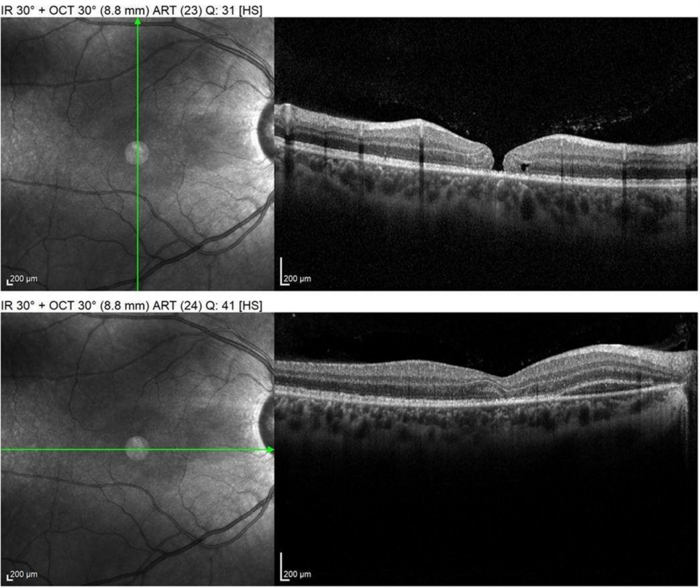

SPECTRALIS OCT shows Macular hole, subretinal hemorrhage, loss of photoreceptor layer.

Image courtesy: Ronald Gentile, MD, FACS, FASRS